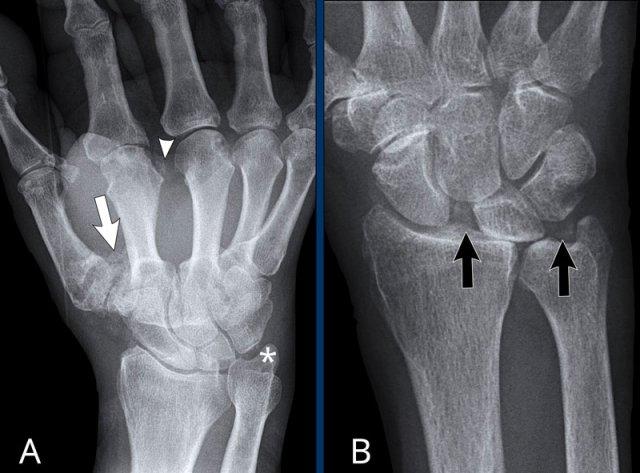

CPPD có thể gây phân ly SL (mũi tên trái). - Vôi hóa sụn trong khớp gối.

- Vôi hóa sụn trong CPPD. Một lần nữa, phân ly SL được ghi nhận, kèm thoái hóa thứ phát nặng. Tình trạng thoái hóa nặng này được gọi là cổ tay SLAC, viết tắt của Scaphoid Lunate Advanced Collapse (Xẹp tiến triển xương thuyền – xương nguyệt).

Hai bệnh nhân với hình ảnh CPPD điển hình.

A. Có mất sụn ở nhiều khớp và vôi hóa sụn tại:

- Khớp CMC1 (mũi tên trắng)

- Các khớp MCP (đầu mũi tên)

- Sụn sợi tam giác TFCC (dấu hoa thị)

B. Bệnh nhân này có viêm khớp cấp tính. Vôi hóa sụn tại khớp quay-cổ tay và sụn sợi tam giác TFCC (mũi tên đen) được ghi nhận, gần như là dấu hiệu đặc trưng bệnh lý của CPPD. Có hình ảnh phân ly xương thuyền-nguyệt, có thể gặp trong CPPD, nhưng cũng gặp trong viêm khớp dạng thấp hoặc sau chấn thương.

Cơn tấn công đột ngột này được gọi là giả gút, vì có thể mô phỏng tình trạng viêm và đau dữ dội của một cơn gút cấp.